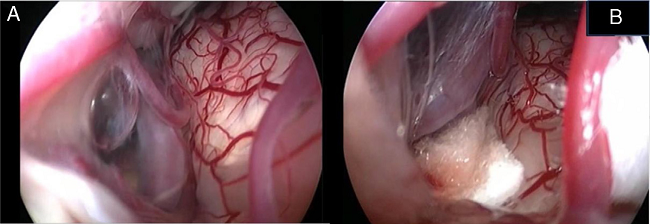

In the retroauricular area, along the proposed lines of incision (Fig. 1), 5-7 mL of 2% lidocaine with 1:100,000 epinephrine are injected to enhance hemostasis and soft tissue dissection. A 6-8 cm skin incision drawn as an arc is performed with the convex side facing posterior. The incision is placed around 1 cm behind the supposed posterior edge of the craniotomy and 2 fingers to the helix projection to the retro-mastoid region. By placing the incision in such area we can preserve both occipital artery and C2 nerve from trauma. A skin flap is elevated anteriorly. A muscle-periosteal incision is carried out with monopolar cautery. Bone drilling for retrosigmoid craniotomy begins around the emissary vein, by keeping it in the center as a landmark. A large cutting burr is used to start the dissection, while a diamond burr is required in proximity to the dura and the sigmoid sinus to preserve their surfaces. A circular craniotomy from 1.5 to 2 cm of diameter is performed back to the sigmoid sinus. The dura is opened in a V-shape manner, starting just behind the sigmoid sinuses to reduce the necessity of cerebellar mechanical retraction during the access to the IAC. Then, the dural incision is performed 1-2 mm from the craniotomy edges to facilitate dural re-suturing at the end of surgery. Anesthesiology hyperventilation is carried out to reduce CSF intra-cranial pressure and spontaneously retract the cerebellum. Once sufficient cerebellar "relaxation" is achieved, a fine neurosurgical cottonoid or Neuropatch (1.5 cm wide by 5 cm long size) is placed over the cerebellum for protection from possible injuries while introducing instruments. The cisterna magna is opened to gain access to the CPA. With the microscope, the arachnoid surrounding the cranial nerves VIII and lower cranial nerves is dissected. The procedure continues by using the endoscope (Rigid 4 mm, 30°, by KARL STORZ®, Tuttlingen, Germany). The acoustic-facial bundle is the central landmark of the CPA and the neurovascular conflict (NVC) area is identified below it at the REZ of the facial nerve. The most common offending vessel is the posterior inferior cerebellar artery (PICA) (Fig. 2A). An additional impinging vessel (anterior inferior cerebellar artery - AICA) is located along the cysternal portion of the facial nerve and sometimes is partially located in the beginning of the internal auditory canal (IAC); a partial drilling of the porus is required and is carried out to allow vessel decompression.

Again, by using the microscope the offending arterial vessel(s) is gently separated from the facial nerve. Sometimes, immediately after facial nerve detachment, a "releasing" trail of electrical stimuli may be noticed on the facial nerve monitoring, which confirms the decompression success.17 Teflon® sponges are the interposed between all offending vessel(s) in order to prevent a new neurovascular contact and to insulate the facial nerve (Fig. 2B). If a vein impinges the facial nerve, after vessel detachment, it is carefully coagulated with bipolar forceps. At the end of the decompression procedure, the proper positioning of the teflon is checked with the endoscope. The cottonoids are removed and the CPA filled with saline solution, then the dura is sutured by single re-absorbable stitches to ensure a water proof resistance. Additional connective tissue is placed and fixed by tissuecole. Bone patè, obtained with bone dust (collected during cranial drilling) fixed by fibrin glue, is used to close the craniotomy site. The muscle-periosteal and cutaneous flaps are carefully sutured in layers with single absorbable stitches. A compressive bandage is applied and kept for 4 days. The patient is awoken from general anesthesia, extubated, lead to the postoperative room for a 3 h observation and then returned to the general ward. The patient permanence is 1 week in the hospital. Patients are followed-up periodically for 2 years after surgery.